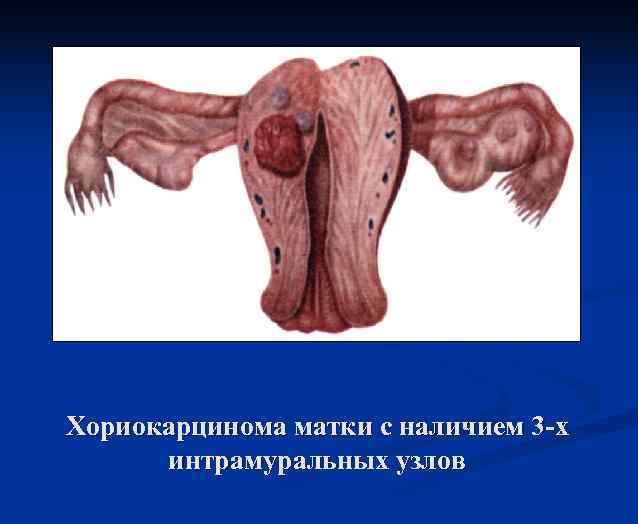

Хориокарцинома матки с наличием 3 -х интрамуральных узлов